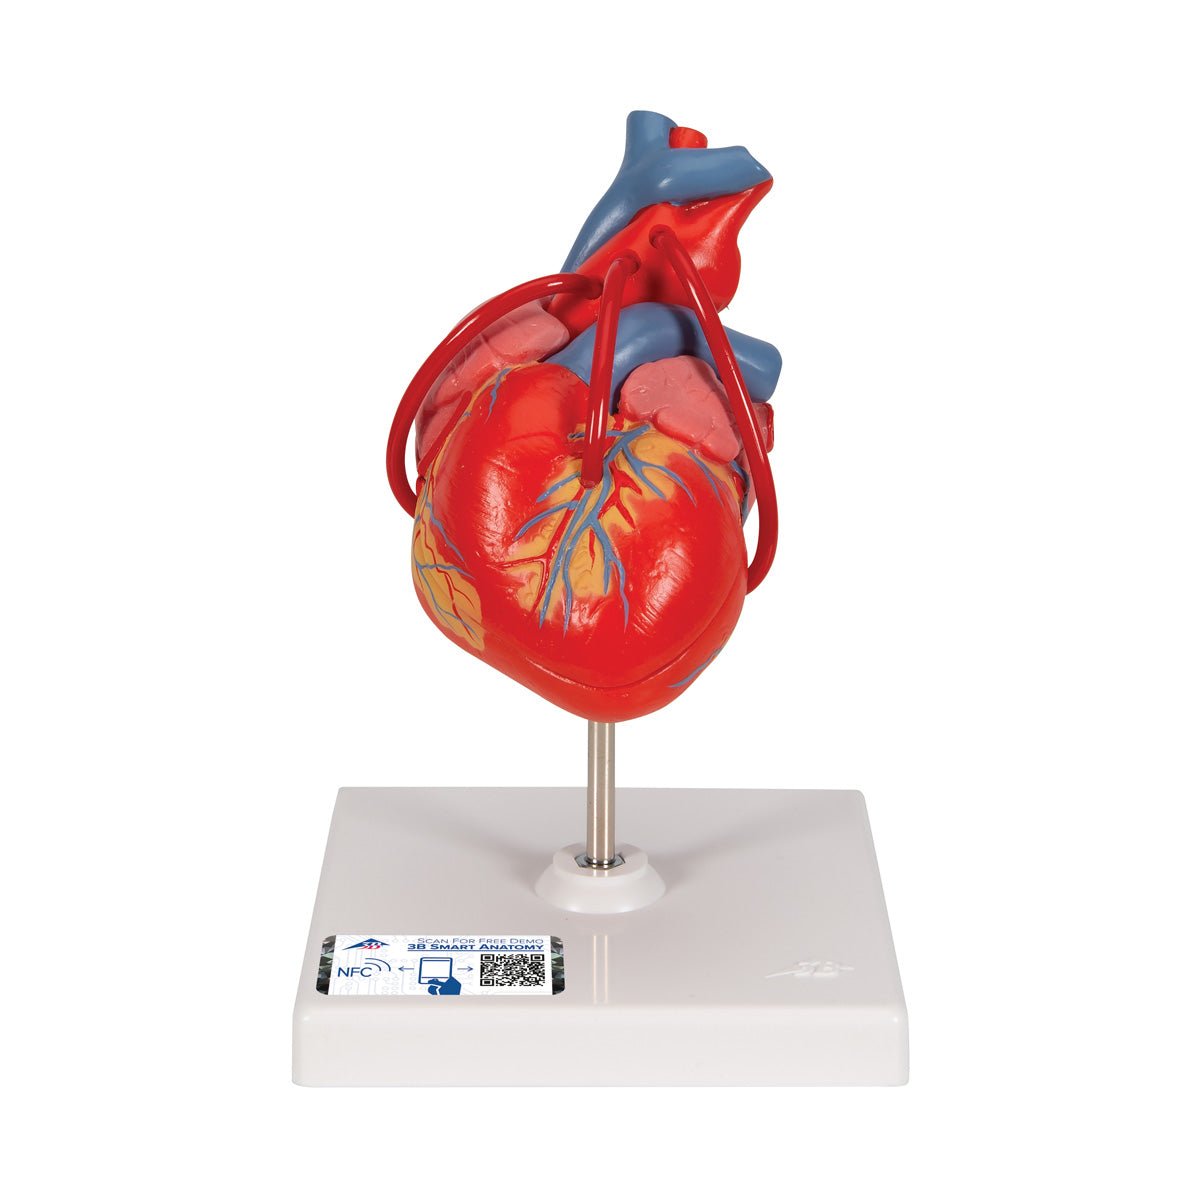

Anatomical models

Selling anatomical models is the mainstay of eAnatomi, although we also spend a lot of resources developing our own anatomical materials such as posters. Anatomical models are used for various purposes and can show both defined tissues, organs and organ systems. Are you looking for a simple model of bone tissue or perhaps an advanced torso model based on MRI technology, you can find it all at eanatomi.com.